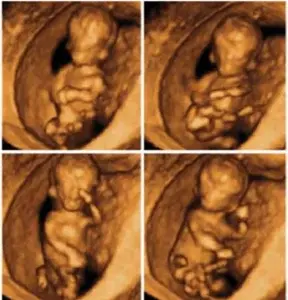

في رحلة الحمل، يصبح كل أسبوع مليئًا بالتغيرات المهمة للجنين، ويزداد فضول الأهل لمعرفة تفاصيل دقيقة عن حالة الجنين وصحته. هنا تأتي أهمية الأشعة رباعية الأبعاد (4D Ultrasound)، التي تمنح الأهل فرصة لرؤية صور حية ومتحركة للجنين داخل رحم الأم. في مركز إيفا للنساء والولادة بالمرج، القاهرة، نوفر أحدث تقنيات الأشعة رباعية الأبعاد لمتابعة صحة الأم وجنينها بدقة وراحة تامة، تحت إشراف فريق طبي متخصص.

الأشعة رباعية الأبعاد من أحدث تقنيات السونار التي تساعد على متابعة الجنين بدقة عالية داخل الرحم. في هذا المقال نوضح متى تحتاج الحامل لهذا الفحص، وما أهميته في الاطمئنان على صحة الجنين، وأفضل وقت لإجرائه لضمان أفضل النتائج.